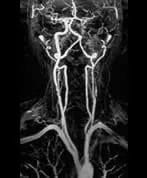

Internal Carotid Artery Stenosis

A patient presents with a known left hemisphere infarct, degree of internal carotid artery stenosis.

There is a critical stenosis of the left internal carotid artery (ICA) at its origin. Moderate irregularity and narrowing of the right ICA is noted at its origin. Carotid Doppler ultrasound quantifies the left ICA stenosis to be greater than 70% and the spectral waveform pattern suggests string flow or a near occlusion. The right ICA stenosis was measured at between 50-59%.